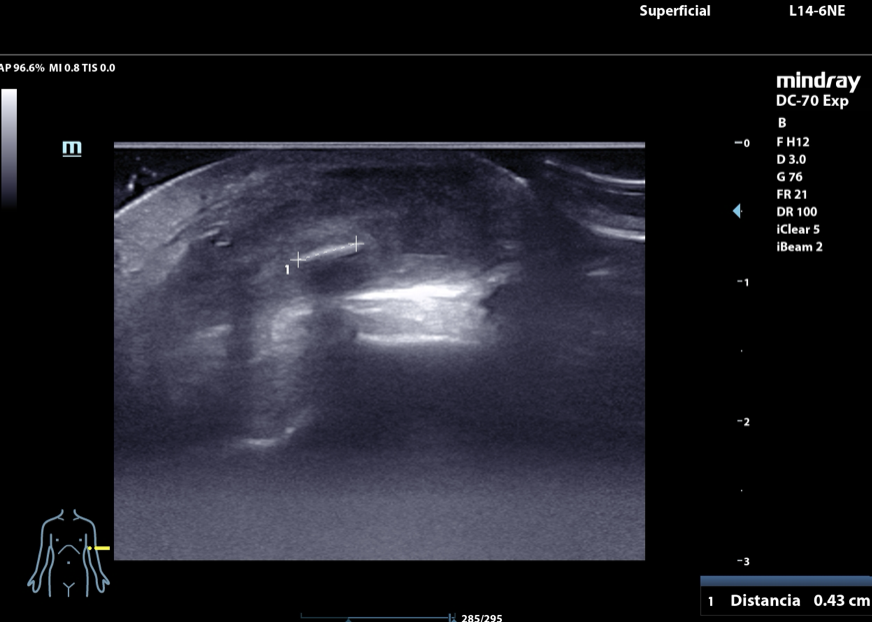

Hombre de 17 años que acude a consulta en agosto de 2024 por dolor y tumefacción a nivel de epicóndilo de codo izquierdo. En abril sufrió una caída contra una palmera y desde ese momento ha consultado hasta en tres ocasiones en Urgencias por dolor. En el informe de urgencias se diagnostica un absceso cutáneo de 1 cm de diámetro y se solicita una radiografía de codo (sin alteraciones). Se alta con antibioterapia. En consulta persiste la sintomatología. Se revisa la radiografía y se repite la exploracion física: tumefacción de 1,5 cm de diámetro en epicóndilo izquierdo. Se decide realizar una ecografía músculoesquelética con identificación de un cuerpo extraño tras lo que se procede a su extracción que resulta ser una púa de 2,6 cm.

Tras la ecografía se procede a la extracción de dicho cuerpo extraño que resulta ser una púa de palmera de 2,6 cm de longitud.

La ecografía es una prueba complementaria accesible desde Atención Primaria, inocua y rápida que permite la identificación de estructuras que, como la descrita en el caso clínico, resultan invisibles a la radiografía convencional, lo cual favorece el logro de diagnósticos más certeros que evitan medidas terapéuticas futiles y la cronificación del dolor musculoesquelético.